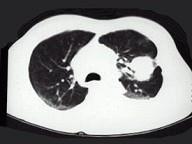

问题 女,68岁,咳嗽伴胸痛胸闷1个月,CT检查如图,最可能的诊断为 ( )

选项 A.左上肺不张 B.左上肺周围型肺癌伴胸膜转移 C.左上肺血管瘤 D.左上肺软骨肉瘤伴胸膜转移 E.左上肺结核

答案 B